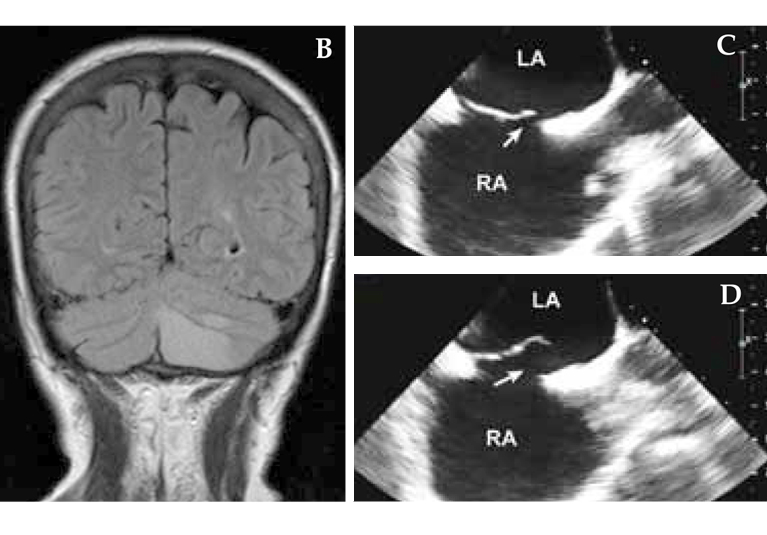

A 63-year-old woman who had a remote history of migraine awakened with a headache with visual aura, as well as nausea, vomiting and incoordination. She was a former smoker but had no history of hypertension, estrogen replacement or family history of stroke. A and B. MRI demonstrated a left cerebellar infarct. C and D. Transesophageal echocardiography demonstrated a large PFO (arrow) with an atrial septal aneurysm. E. Contrast injection demonstrated generous flow across the PFO (arrow) with Valsalva. Percutaneous closure was performed. LA, left atrium; RA, right atrium.

The prevalence of PFO in the adult general population may be as high as 25 percent; usually these interatrial shunts are asymptomatic and of no hemodynamic importance. Until the advent of echocardiography, it was difficult to diagnose PFO antemortem. Transthoracic imaging, especially with agitated saline contrast injection, transesophageal echocardiography and transcranial Doppler, is widely used to identify and characterize PFO.